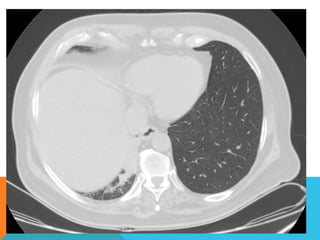

En los cortes realizados hacia las bases pulmonares es posible delimitar los órganos sólidos intraabdominales

tales como el hígado sin anormalidades que consignar; se demuestra imagen hiperdensa puntiforme en

topografía del parénquima esplénico en relación a calcificación inespecífica. Hay distensión aérea esofágica

que lo define prácticamente su totalidad.

Se demuestran imágenes hiperdensas en topografía intraluminal vesicular que corresponden con colelitiasis.

Se define imagen hipodensa parenquimatosa renal superior derecha con patrón de atenuación homogéneo,

líquido que condiciona la sospecha de lesión focal benigna tipo quística simple.

INTERPRETACIÓN DIAGNÓSTICA:

ESTUDIO ANORMAL QUE DEMUESTRA HALLAZGO INESPECIFICO DE SOBREDISTENSIÓN PULMONAR  CON

CAMBIOS FIBROSOS CICATRICIALES APICALES DERECHOS Y ÁREAS DE CONDENSACIÓN PARENQUIMATOSAS

PULMONARES, DE PREDOMINIO DERECHO, LA DE MAYORES DIMENSIONES BASAL DERECHA, ASOCIADA CON

BRONCOGRAMA AÉREO.

COLELITIASIS.

ABORDAJE TÉCNICO: Serealiza estudio con ventana mediastinal y de parénquima pulmonar con técnica de ALTA RESOLUCION, en inspiración y espiración, mediante  cortes axiales, desde ápices hasta bases pulmonares, con las siguientes observaciones En las partes blandas y las estructuras óseas dentro de los límites de la normalidad. Las regiones axilares libres. Ambos pulmones con neumatización conservada, con sobredistensión pulmonar, y áreas de atrapamiento aéreo, bilateral con cambios fibrosos cicatriciales apicales derechos. Se demuestran áreas de condensación en topografía predominantemente parenquimatosa pulmonar derecha, la mayor de ellas evidenciada hacia la base, acompañada de broncograma aéreo, la medición máxima al corte axial de 6.1 por 2.2 cm, en topografía del segmento posterior del lóbulo inferior, S10 así como también otra más se definen topografía de similares características en topografía del segmento medial del lóbulo medio, S5. En topografía parenquimatosa pulmonar izquierda imagen de similares características a las ya descritas en topografía del segmento lingular inferior, S4. No hay derrame ni áreas de engrosamiento pleurales. El patrón vascular es de características normales donde no se delimitan imágenes de lesiones aneurismáticas únicamente cambios por aortoesclerosis incipiente. El corazón de dimensiones conservada, de contornos regulares, sin desplazamientos; en la región hiliar derecha se define adenopatía de medición máxima corte axial de 1.6 por 1.4 cm.

En los cortesrealizados hacia las bases pulmonares es posible delimitar los órganos sólidos intraabdominales tales como el hígado sin anormalidades que consignar; se demuestra imagen hiperdensa puntiforme en topografía del parénquima esplénico en relación a calcificación inespecífica. Hay distensión aérea esofágica que lo define prácticamente su totalidad. Se demuestran imágenes hiperdensas en topografía intraluminal vesicular que corresponden con colelitiasis. Se define imagen hipodensa parenquimatosa renal superior derecha con patrón de atenuación homogéneo, líquido que condiciona la sospecha de lesión focal benigna tipo quística simple. INTERPRETACIÓN DIAGNÓSTICA:   ESTUDIO ANORMAL QUE DEMUESTRA HALLAZGO INESPECIFICO DE SOBREDISTENSIÓN PULMONAR  CON CAMBIOS FIBROSOS CICATRICIALES APICALES DERECHOS Y ÁREAS DE CONDENSACIÓN PARENQUIMATOSAS PULMONARES, DE PREDOMINIO DERECHO, LA DE MAYORES DIMENSIONES BASAL DERECHA, ASOCIADA CON BRONCOGRAMA AÉREO. COLELITIASIS.